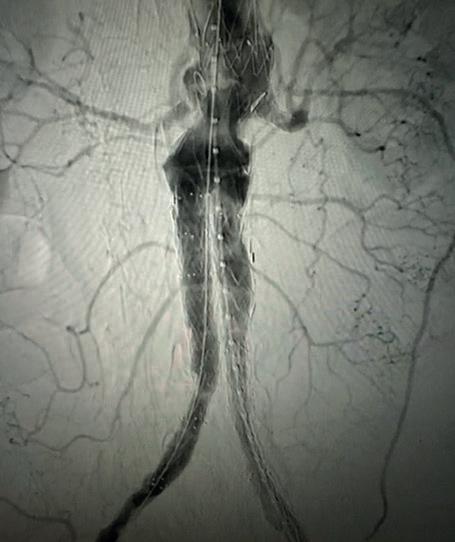

Case 1: The Shockwave L6 device in the setting of FEVAR and complex iliac stenosis

An 82-year-old man with a history of coronary artery disease (CAD), hypertension, hyperlipidemia, and peripheral arterial disease (PAD) presents with rest pain as well as

a large pararenal abdominal aortic aneurysm (AAA). His computed tomography angiography (CTA) revealed very dense and highly diseased iliac vessels with calcium deposition along most of the bilateral common iliac distribution.

The minimum luminal diameter (MLD) of the common iliac arteries measured roughly 4.5mm; however, the

healthy reference vessel diameter (RVD) was 9.5mm. He would require a fenestrated repair of the AAA along with complex iliac stenosis treatment, and extensive bilateral common femoral endarterectomies.

Further, we were concerned we would not be able to advance the 19F fenestrated graft. The endograft was prepared, and then both femoral arteries were exposed. We attempted delivery of the endograft via the right common iliac access. This failed. We then attempted delivery on the contralateral side. Despite multiple attempts, we made little progress. A 10x30mm Shockwave L 6 catheter was selected, and a total of 150 pulses were delivered to each iliac artery at just 4atm. This not only allowed for the delivery of our FEVAR graft but also the full unrestricted expansion of the endograft limbs in the common iliac arteries.

At the completion of the AAA, we took extra time to perform endarterectomies of the deep femoral arteries. His completion CT scan revealed a good seal of the AAA, patency of the renal fenestrations and unrestricted flow to the bilateral femoral arteries.

This is a great example of how IVL can be used as a standalone therapy without the need for adjunctive treatment.

MLD = 4.5mm RVD = 9.5mm IVL Device Choice = Shockwave L6 10mm

Figure 1. Pre-procdural CTA Figure 4. Graft delivery Figure 1. Pre-procedural angiogram Figure 2. Pre-procedural angiogram Figure 5. Final angiogram Figure 2. IVL treatment angiogram Figure 3. Post-IVL angiogram Figure 6. Post-procedural CTA Figure 3. Final angiogram